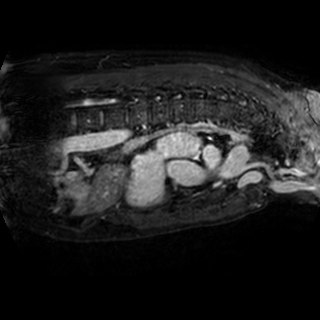

The integration of deep learning systems into healthcare has been hindered by the resource-intensive process of data annotation and the inability of these systems to generalize to different data distributions. Foundation models, which are models pre-trained on large datasets, have emerged as a solution to reduce reliance on annotated data and enhance model generalizability and robustness. DINOv2 is an open-source foundation model pre-trained with self-supervised learning on 142 million curated natural images that exhibits promising capabilities across various vision tasks. Nevertheless, a critical question remains unanswered regarding DINOv2's adaptability to radiological imaging, and whether its features are sufficiently general to benefit radiology image analysis. Therefore, this study comprehensively evaluates DINOv2 for radiology, conducting over 100 experiments across diverse modalities (X-ray, CT, and MRI). To measure the effectiveness and generalizability of DINOv2's feature representations, we analyze the model across medical image analysis tasks including disease classification and organ segmentation on both 2D and 3D images, and under different settings like kNN, few-shot learning, linear-probing, end-to-end fine-tuning, and parameter-efficient fine-tuning. Comparative analyses with established supervised, self-supervised, and weakly-supervised models reveal DINOv2's superior performance and cross-task generalizability. The findings contribute insights to potential avenues for optimizing pre-training strategies for medical imaging and enhancing the broader understanding of DINOv2's role in bridging the gap between natural and radiological image analysis. Our code is available at https://github.com/MohammedSB/DINOv2ForRadiology